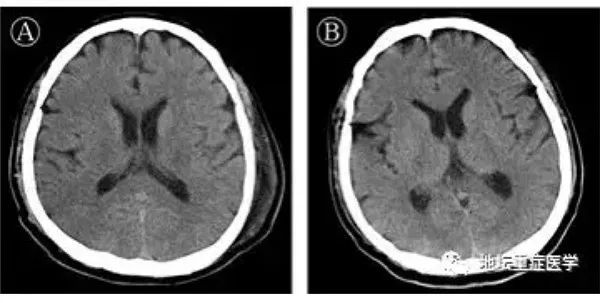

登录/注册后可看大图

据报道,2月25日,56岁的许先生(新冠肺炎危重型、合并脑炎)终于走出北京地坛医院的大门。此前,新冠肺炎患者可合并急性呼吸窘迫综合征兆(ARDS)、心肌损害、凝血功能异常、肾脏损伤、肝脏损害等多脏器损害,尚未发现有中枢神经系统受累的报道,此病例在全球尚属首例。